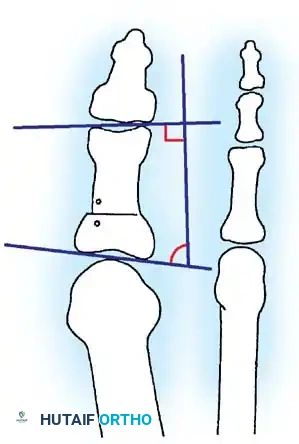

Inadequate vascularity or sensibility should be investigated thoroughly before bunion surgery is considered. In addition, the position of the articular surface of the metatarsal head in relation to the longitudinal axis of the fi rst metatarsal should be determined (Fig. 78-8). Standard preoperative radiographs should include standing dorsoplantar and lateral views, a nonstanding lateral oblique view, and axial sesamoid views (Fig. 78-9). The hallux valgus angle and the fi rst-second intermetatarsal angle should fi rst be drawn on the standing dorsoplantar view by bisecting the shafts of the bones (Fig. 78-10), with an awareness of the normal ranges. These angles are most frequently cited as guidelines for treatment decisions, but Donnelly et al. reported that interobserver measurements of the hallux valgus angle varied by approximately 6 degrees and of the intermetatarsal angle by 4 degrees. They cautioned that potential errors in measurement should be considered when these parameters are used to make treatment decisions. The hallux valgus interphalangeus angle and any evidence of degenerative arthritic changes at the fi rst metatarsophalangeal or metatarsocuneiform joints should be documented. Oddities may be present and, if overlooked, may compromise a technically well-done procedure. Mann emphasized that the presence of an os inter-

Fig. 78-8 A, Determination of position of articular surface of metatarsal head in relation to longitudinal axis of fi rst metatarsal. B, Measurement of distal metatarsal articular angle at time of surgery. Markings are at medial and lateral margins of articular surface of fi rst metatarsal head and longitudinal axis of fi rst metatarsal shaft. metatarseum between the bases of the fi rst and second metatarsals might preclude the effectiveness of a soft-tissue procedure alone to provide suffi cient correction of the increased intermetatarsal angle. Likewise, accessory sesamoids and prominent ungual tuberosities at the interphalangeal joint contribute to a painful callus at the tibial side of this joint. An os tibialis externum frequently is associated with excessive hallux valgus interphalangeus. Varus of the fi rst metatarsal might be a signifi cant part of the overall deformity of the foot even with an intermetatarsal angle of less than 10 degrees. Metatarsus varus with a relatively small hallux valgus angle (15 to 20 degrees) may produce signifi cant deformity even though the angles are not excessive. The usefulness of computer-assisted compared with manual measurement of the intermetatarsal angle, hallux valgus angle, and distal metatarsal articular angle is still uncertain. Both methods have closer interobserver and intraobserver correlation in measurement of the intermetatarsal angle and hallux valgus angle than in measurement of the distal metatarsal articular angle. The reliability of either method has such a wide range (5 degrees), however, that measurements of these angles, although useful as a guide, do not provide a completely reliable indication of the magnitude of deformity. Condon et al. suggested that the reliability of the intermetatarsal angle can be improved by careful technique and by making the measurements at least twice and averaging them. Schneider et al. reported two methods of determining angular measurements based on distinctly different reference points: (1) a longitudinal axis of the fi rst metatarsal using middiaphyseal reference points, and (2) a center-head technique using a center head (center of the articular surface) and center base

(center of the proximal diaphysis) as reference points. They found that measured correction of the hallux valgus and intermetatarsal angles varied by approximately 9 degrees depending on which reference points were used. Recommendations of Coughlin, Saltzman, and Nunley (American Orthopaedic Foot and Ankle Society Ad Hoc Committee on Angular Measurements) included standardized radiographic technique, specifi c placement of reference points (Fig. 78-11), use of a protractor rather than a goniometer for measurements, and, after distal osteotomies, dual measurements using a center-head technique and a Mose sphere.

Fig. 78-10 Method of measuring hallux valgus angle and intermetatarsal angle. Center points are connected, and intersecting lines defi ne angles.